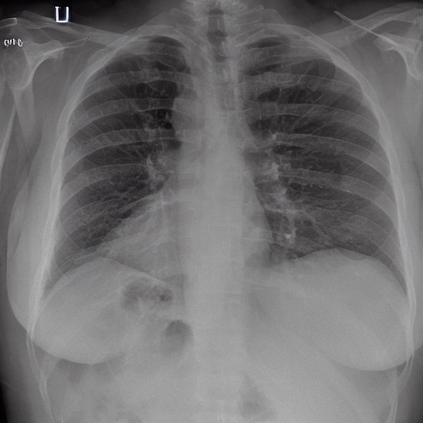

To address these issues, we propose a novel Adaptive patch-word Matching (AdaMatch) model to correlate chest X-ray (CXR) image regions with words in medical reports and apply it to CXR-report generation to provide explainability for the generation process. AdaMatch exploits the fine-grained relation between adaptive patches and words to provide explanations of specific image regions with corresponding words. To capture the abnormal regions of varying sizes and positions, we introduce the Adaptive Patch extraction (AdaPatch) module to acquire the adaptive patches for these regions adaptively. In order to provide explicit explainability for CXR-report generation task, we propose an AdaMatch-based bidirectional large language model for Cyclic CXR-report generation (AdaMatch-Cyclic). It employs the AdaMatch to obtain the keywords for CXR images and `keypatches' for medical reports as hints to guide CXR-report generation. Extensive experiments on two publicly available CXR datasets prove the effectiveness of our method and its superior performance to existing methods.